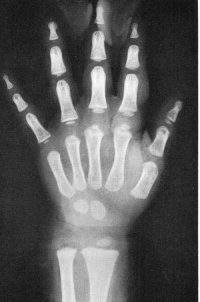

Sexo Masculino

Recém-Nascido

idade óssea - RN